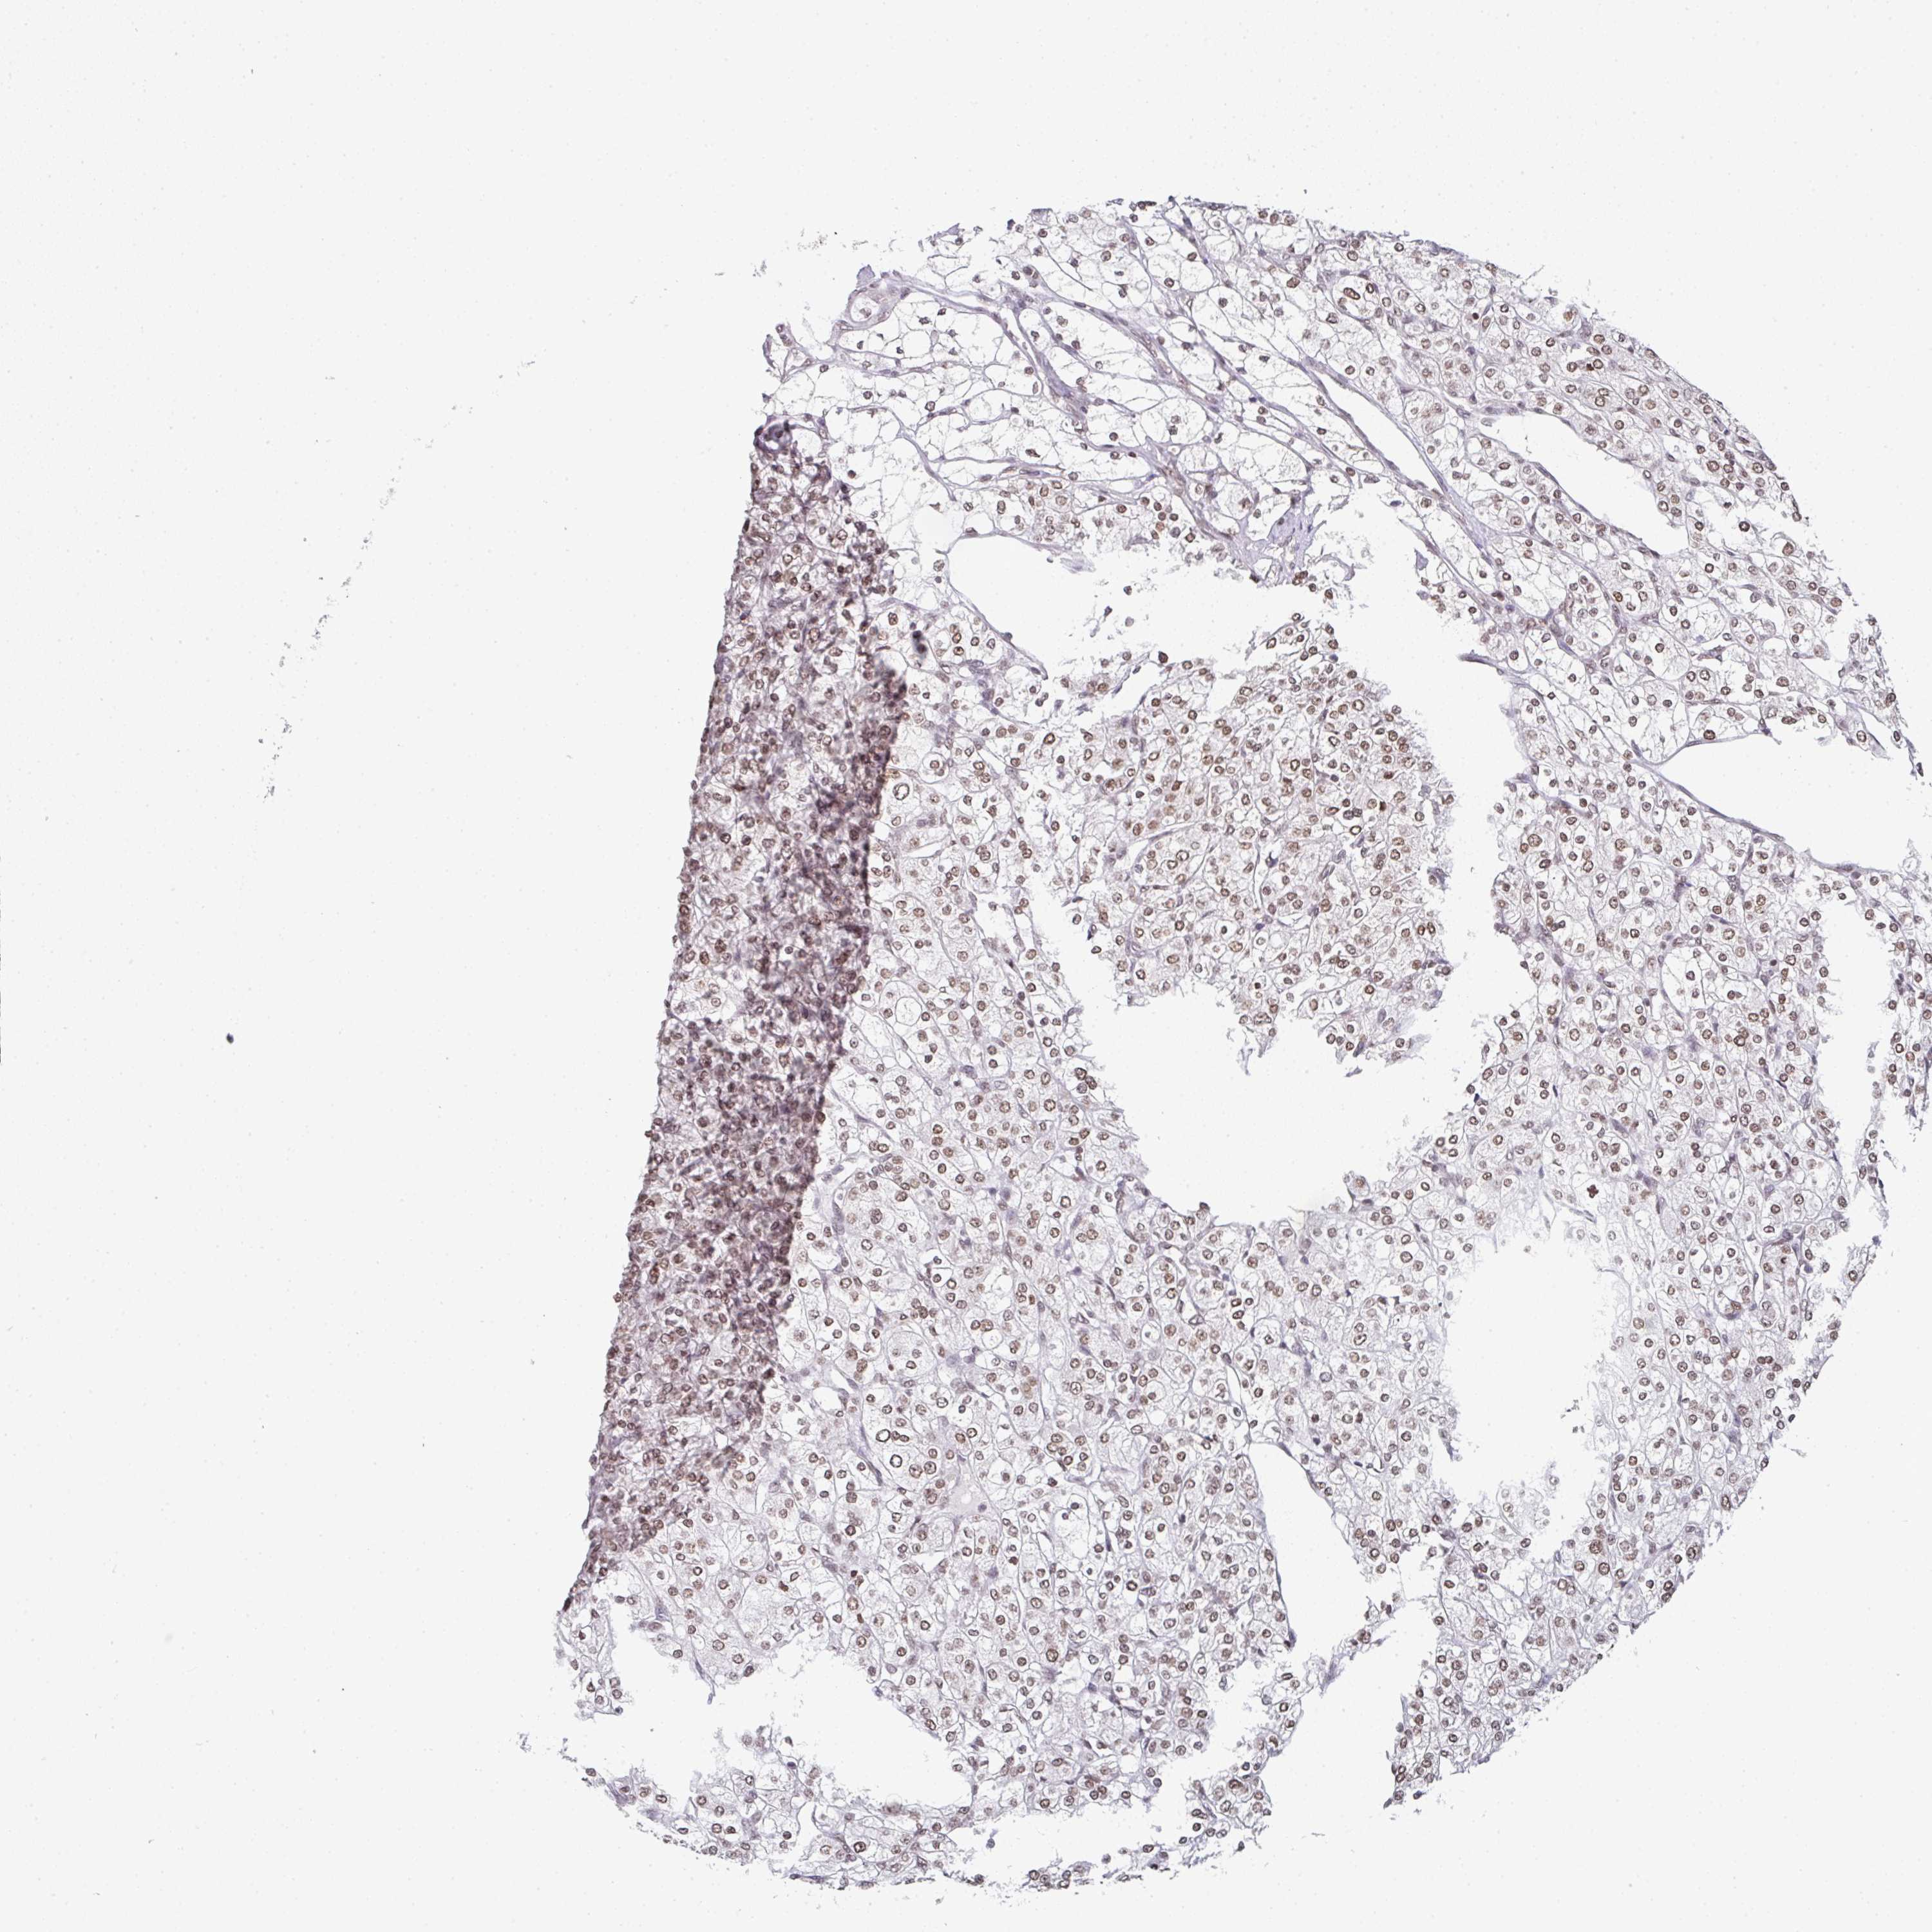

KIDNEY RENAL CLEAR CELL CARCINOMA (VALIDATION) - Interactive survival scatter ploti

The Survival Scatter plot shows the clinical status (i.e. dead or alive) for all individuals in the patient cohort, based on the same data that underlies the corresponding Kaplan-Meier plots. Patients that are alive at last time for follow-up are shown in blue and patients who have died during the study are shown in red.

The x-axis shows the expression levels (FPKM) of the investigated gene in the tumor tissue at the time of diagnosis. The y-axis shows the follow-up time after diagnosis (years). Both axes are complimented with kernel density curves demonstrating the data density over the axes. The top density plot shows the expression levels (FPKM) distribution among dead (red) and alive patients (blue). The right density plot shows the data density of the survived years of dead patients with high and low expression levels respectively, stratified using the cutoff indicated by the vertical dashed line through the Survival Scatter plot. This cutoff is automatically defined based on the FPKM cutoff that minimizes the p-score. The cutoff can be changed by dragging the vertical line or by entering a cutoff value in the square labeled "Current cut-off".

Under the Survival Scatter plot the p-score landscape (black curve; left axis) is shown together with dead median separation (red curve; right axis). Dead median separation is the difference in median mRNA expression between patients who have died with high and low expression, respectively. It is calculated as follows: median FPKM expression of dead patients with high expression - median FPKM expression of dead patients with low expression. This is intended to aid the user in visually exploring custom cutoffs and the associated p-scores and dead median separation.

Individual patient data is displayed and can be filtered by clicking on one or more of the category buttons on the top of the page. Categories describing expression level and patient information include: high, low, alive, dead, female, male and tumor stages. The scale of the x-axis can be toggled between linear and log-scale by clicking on the "x log" button. Mouse-over function shows TCGA ID, patient information and mRNA expression (FPKM) for each patient.

& Survival analysisi

Kaplan-Meier plots summarize results from analysis of correlation between mRNA expression level and patient survival. Patients were divided based on level of expression into one of the two groups "low" (under cut off) or "high" (over cut off). X-axis shows time for survival (years) and y-axis shows the probability of survival, where 1.0 corresponds to 100 percent.

DKC1 is not prognostic in Kidney Renal Clear Cell Carcinoma (validation)

Best expression cut offi

Based on the FPKM value of each gene, patients were classified into two groups and association between prognosis (survival) and gene expression (FPKM) was examined. The best expression cut-off refers the FPKM value that yields maximal difference with regard to survival between the two groups at the lowest log-rank P-value. Best expression cut-off was selected based on survival analysis .

When clicking on this number, the vertical dashed line indicating cut-off, the interactive survival plot, and the Kaplan-Meier curve will be adjusted to show results based on the best expression cut-off.

: 32.21

P scorei

Log-rank P value for Kaplan-Meier plot showing results from analysis of correlation between mRNA expression level and patient survival.

N/A

TCGA RNA samplesi

RNA-seq data is reported as average FPKM (number Fragments Per Kilobase of exon per Million reads), generated by the The Cancer Genome Atlas (TCGA) .

Normal distribution across the dataset is visualized with box plots, shown as median and 25th and 75th percentiles. Points are displayed as outliers if they are above or below 1.5 times the interquartile range. FPKM values of the individual samples are presented next to the box plot.

Average pTPM 28.1

Number of samples 100